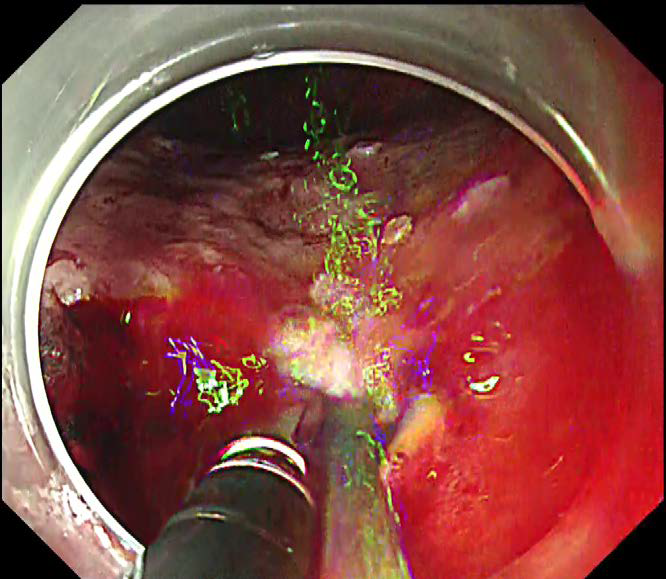

内視鏡画面上での処置具の見え方 |

| |